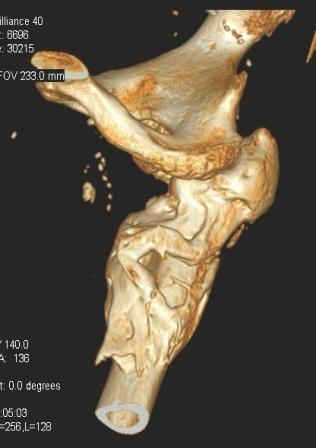

Уважаемый Глеб! Укорочение наверное побольше, да и наружно-ротационная установка скорее всего присутствует. Суставная щель прекрасная, головка живее всех живых. Ратую за подвертельную с латерализацией: исключает нарушение механической оси («исключает вальгус в коленe»), максимально удлиняет без натяжения m.iliacus. Для иллюстрации остеотомия-переделка (слава богу не автопеределка) у мужчины 65 лет.

Филипчук.

PS. Извините за качество последнего снимка, рентгенограмма выполнена по м. жительства, там где был проведен синтез. Последний снимок выполнен через 2 мес. п\о, больной без разрешения начал наступать, слава богу все обошлось.